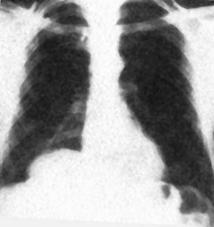

Hemotorace stang masiv Hemotorace stang masiv

Hemotorace

drept masiv Hemotorace stang

Imagine CT Radiografie efectuata in ortostatism

Hemotorace drept Hemo-pneumotorace stang

Radiografie efectuata in clinostatism